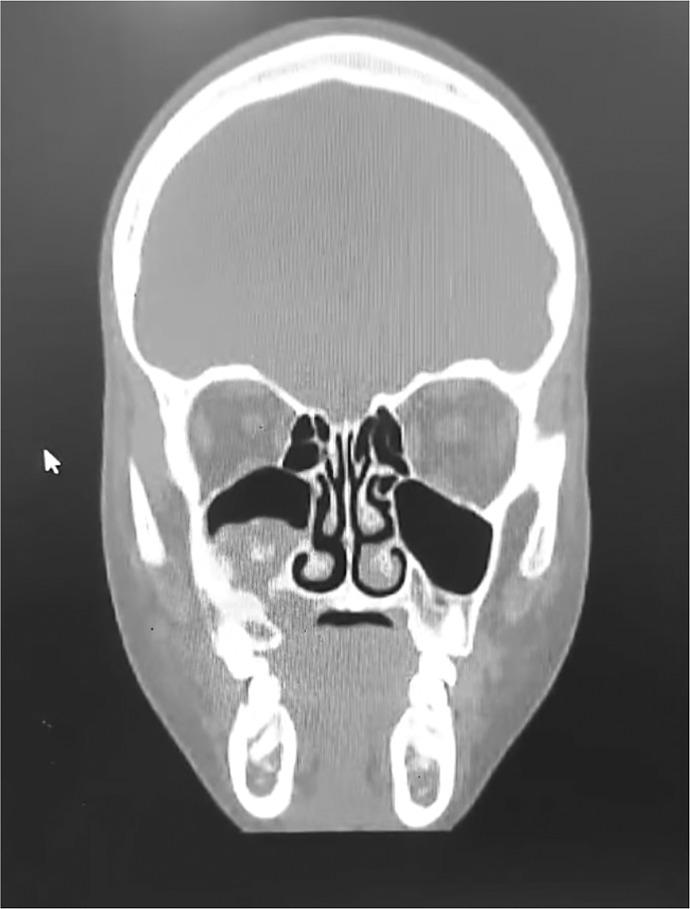

This case report details a 14-year-old Arab female with maxillary ES, highlighting diagnostic and therapeutic challenges. The patient presented with jaw pain and swelling, initially evaluated via radiography and biopsy, revealing classic histopathological features (small round blue cells, Homer-Wright rosettes) and immunohistochemical markers (CD99, NKX2.2, FLI1 positivity). Imaging identified a localized maxillary mass (T4a N0 M0). Multimodal therapy included neoadjuvant chemotherapy (VDC/IE regimen), en bloc resection, adjuvant chemotherapy, and dental rehabilitation.

本病例报告详细介绍了一名患有上颌骨ES的14岁阿拉伯女性,突出了诊断和治疗方面的挑战。患者表现为颌部疼痛和肿胀,最初通过X线摄影和活检进行评估,显示出典型的组织病理学特征(小圆蓝细胞、霍纳-赖特玫瑰花结)和免疫组化标志物(CD99、NKX2.2、FLI1阳性)。影像学检查发现一个局限性上颌骨肿块(T4a N0 M0)。多模式治疗包括新辅助化疗(VDC/IE方案)、整块切除、辅助化疗和牙齿修复。